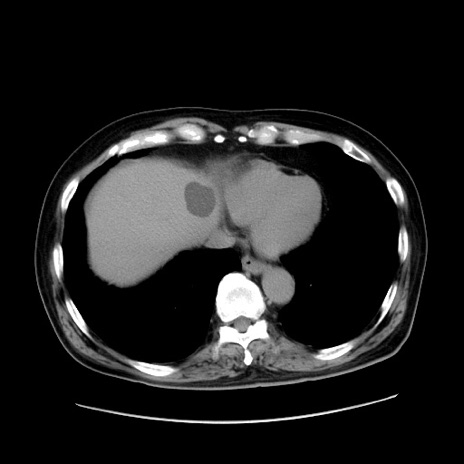

冠状断像